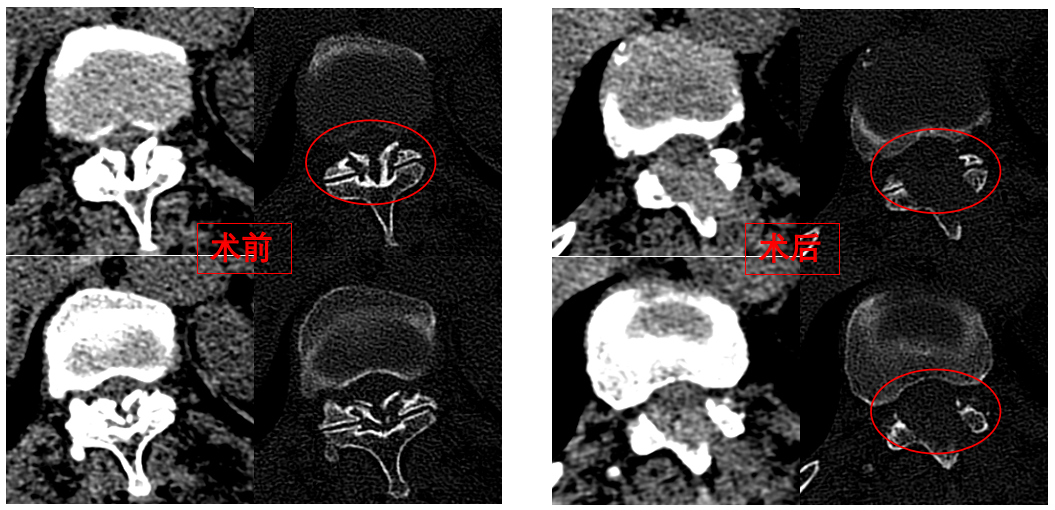

華西醫(yī)院成辦分院骨科副主任醫(yī)師張斌接診后,憑借豐富的脊柱治療經(jīng)驗(yàn),立即安排卓瑪阿媽做了系列精密檢查,檢查結(jié)果顯示,阿媽胸椎11/12節(jié)段黃韌帶嚴(yán)重骨化,導(dǎo)致椎管顯著狹窄,脊髓受壓,確診為嚴(yán)重的“胸椎黃韌帶骨化癥”,如果不及時(shí)手術(shù)最終可能面臨癱瘓的風(fēng)險(xiǎn)。

手術(shù)歷時(shí)一個(gè)半小時(shí),骨科脊柱微創(chuàng)團(tuán)隊(duì)成功完整切除了壓迫脊髓的骨化黃韌帶,徹底解除了卓瑪阿媽的脊髓壓迫。手術(shù)過程順利,手術(shù)切口僅1厘米。

圖為卓瑪阿媽術(shù)前、術(shù)后胸椎CT照片對比。